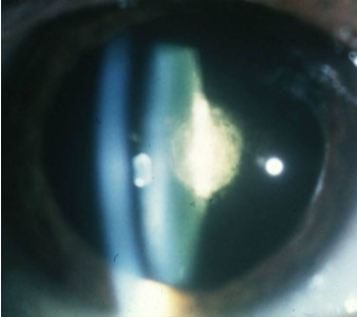

pseudoexfoliation syndrome

etiology: amyloid amorphous material secreted by CB epithelium, deposited on the anterior lens capsule, posterior iris, ciliary processes, & TM

usually bilateral

can lead to secondary glaucoma